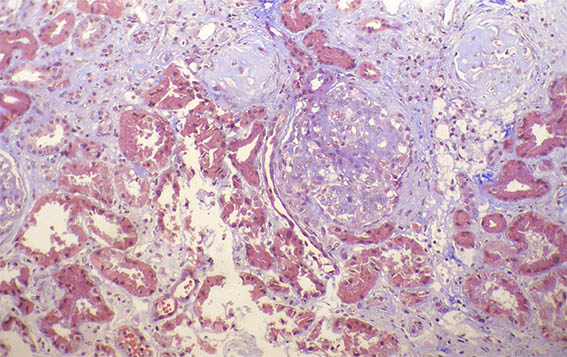

Figure 1. Masson's trichrome, X100.